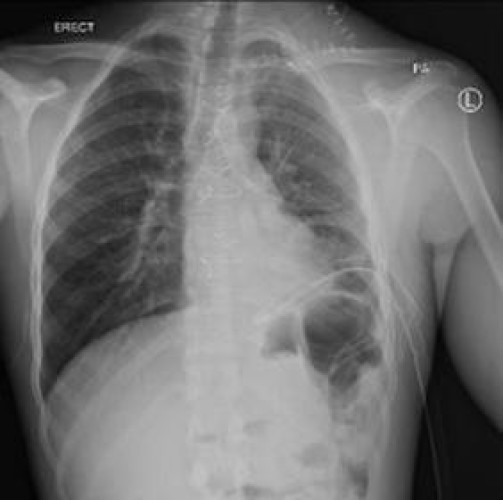

وأوضح “التجمع الأول” أن المصاب قد تعرض لحالة الطعن مساء يوم الأربعاء الماضي وقد تلقى العلاج المبدئي والتعامل مع النزيف في مستشفى الأفلاج العام، وتم التواصل مع مركز الإحالات؛ ليتم نقل المريض بشكل طارئ إلى المدينة الطبية، حيث تم إستقبال المصاب في منتصف الليل، وعلى الفور تم إيقاف النزيف بعد أخذ المصاب لغرفة العمليات، وعمل شق جراحي أعلى عظمة الترقوة اليسرى، ومن ثم فتح الصدر بواسطة شق عظمة القص؛ حيث تبيّن أن المصاب قد نزف ما يقارب من 2 إلى 3 لتر من الدم في التجويف الصدري، ليتم التحكم بالنزيف وإعطاء المصاب ما يقارب 15 من وحدات الدم أثناء العملية.

وأشار “التجمع الأول” بأن العملية تكللت بالنجاح ولله الحمد وخرج المريض من المستشفى وهو بصحة جيدة، وذلك بعد عمل أشعة مقطعية بالصبغة للطرف العلوي الأيسر له؛ حيث تم التأكد من توقف النزيف، وتتم متابعة المريض حالياً في العيادات الخارجية.